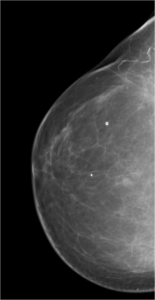

52 year old lady who underwent wide local excision for stage I breast carcinoma of right breast 7 years ago has presented for routine screening mammogram.

Ductal Cell carcinoma In Situ-DCIS RIGHT BREAST.(Comedo and cribriform type)

Craniocaudal and mediolateral oblique views of both the breast.Post operative scar is seen in the upper and outer quadrant of right breast.Pleomorphic calcifications,predominantly showing fine linear branching pattern( comedo pattern) is seen in segmental distribution with nipple convergence in the central right breast.